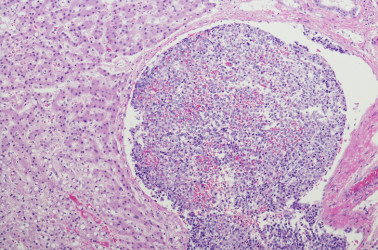

कैंसर

कैंसर